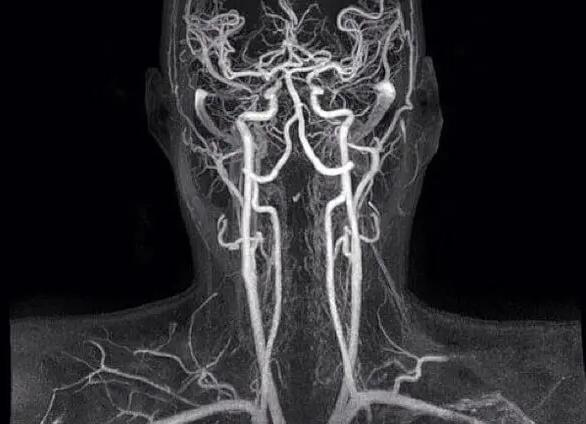

Перед тем как лечить спазмы сосудов головного мозга, проводят диагностику посредством различных лучевых методик. Кроме того, одним из способов обнаружения этой аномалии является ЭКГ (электрокардиограмма). Наиболее часто применяют:

Лечение при частых церебральных ангиоспазмах должно быть направлено на устранение причины их возникновения. Для ее выявления проводится ряд диагностических процедур, среди которых дуплексное ультразвуковое сканирование сосудов головы и шеи, рентгенограмма верхнего отдела позвоночника, магнитно-резонансную и компьютерную томографию сосудов головы с контрастированием, магнитно-резонансную ангиографию. Кроме того, с целью исключения некоторых болезней могут потребоваться анализы крови, мочи и пр. Если причину возникновения спазмов сосудов удастся определить и устранить, то все неприятные симптомы исчезнут самостоятельно.

При возникновении вышеперечисленных признаков, необходимо пройти обследование. Для диагностики применяются следующие методики:

• магнитно-резонансная томография внутричерепных и шейных сосудов;

• ультразвуковое обследование шейного участка позвоночника.

Внезапно возникающие сосудистые спазмы в мозге (вазоспазмы) не подтверждаются никакими диагностическими исследованиями, если только инструментальная диагностика не проводится во время приступа головной боли. Органические патологии, провоцирующие стойкое сужение церебральных сосудов, диагностируются при проведении следующих исследований:

• анализ крови — повышенный протромбин, холестерин;

• рентген — повышенное внутричерепное давление проявляется «вдавлениями» на висках;

• ультразвуковой допплер мозга — выявляет сосудистую церебральную патологию у новорожденных (сосуды исследуются через незакрытый большой родничок);

• ангиография мозга, КТ/МРТ — определяют места сужения сосудов и вызвавшую их церебральную патологию.

Спазм сосудов головного мозга нельзя оставлять без внимания. В случае появления вышеперечисленных признаков, нужно пройти специальное обследование. Для диагностики используются следующие методики:

• ультразвуковое исследование шейного отдела позвоночника;

• магнитно-резонансная томография шейных и внутричерепных сосудов.

Тактика лечения в большинстве случаев напрямую зависит от причины болезни. Чтобы восстановить нормальную деятельность кровеносной системы головного мозга, нужно пройти комплексное обследование, после которого врач сможет составить подробный анамнез и определиться с назначаемой терапией. Пациентов направляют на ультразвуковое исследование брахицефальных артерий и магнитно-резонансную томографию шейного отдела позвоночника (нередко провоцирующим спазмы фактором служит остеохондроз). Также потребуется сдача общих анализов и проведение ангиографии для оценки проходимости вен и артерий.